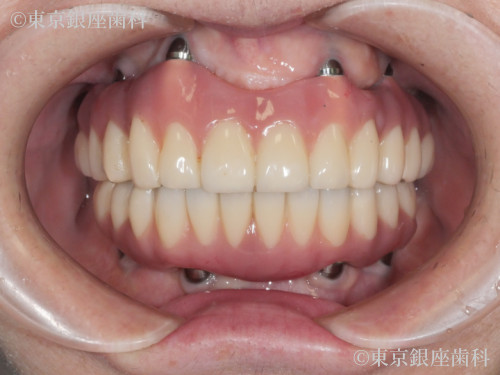

After

重度歯周病で上下インプラントを選択。治療後、顔の赤みが改善し噛む機能も回復。補綴の形態修正も行い自然で快適な仕上がりに。

上下ワンデイインプラント